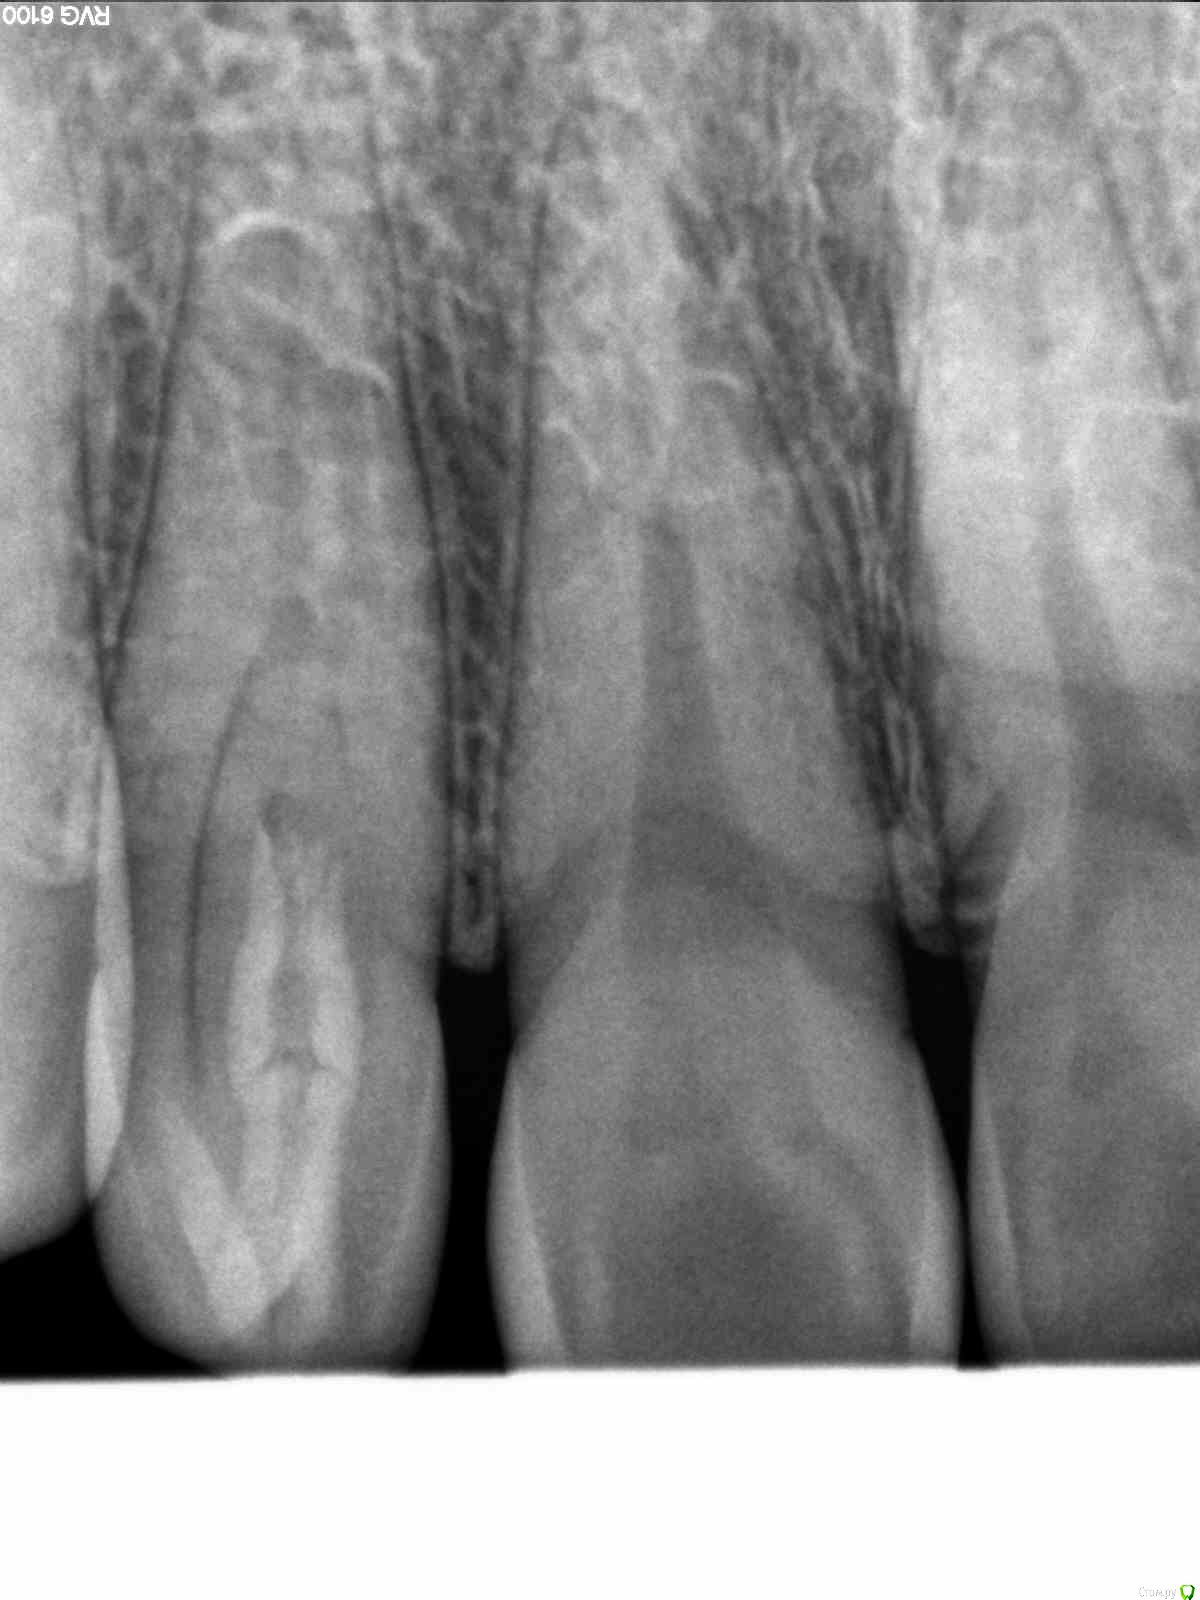

zzkz Опубликовано 5 декабря, 2014 Поделиться Опубликовано 5 декабря, 2014 Коллеги. Вот такой образец на днях попался. Зуб 12.Жалобы пациента на реакцию на холодное.На режущем крае маленькая точка при зондировании которой резкая боль. Мне напоминает апикальное отверстие.Пока закрыл жидким. боль стихла. Отпустил, чтобы подумать и принять решение.Что с ней делать? Ссылка на комментарий

parallax Опубликовано 5 декабря, 2014 Поделиться Опубликовано 5 декабря, 2014 Если судить по снимку, похоже на диагноз "зуб в зубе". 1 Ссылка на комментарий

Kolchanov Опубликовано 5 декабря, 2014 Поделиться Опубликовано 5 декабря, 2014 (изменено) Dens invaginatus То ли первый, то ли третий тип. Изменено 5 декабря, 2014 пользователем Kolchanov Ссылка на комментарий

zzkz Опубликовано 5 декабря, 2014 Автор Поделиться Опубликовано 5 декабря, 2014 Только отьверстие прям по центру режущего края.Что с таким делать? Если боль не прекратиться Ссылка на комментарий